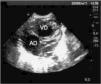

Se trata de una mujer de 17 años, primigesta, sin antecedentes de interés y en gestación de 35 semanas sin control obstétrico. Refiere consumo repetido de metamizol al final del tercer trimestre por odontalgia. La primera ecografía realizada a las 33 + 5 semanas fue normal. En ecocardiografía fetal de control a las 35 semanas se objetiva dilatación severa de cavidades derechas con ventrículo derecho hipertrófico e hipoquinético, insuficiencia tricuspídea y dilatación aguda de la arteria pulmonar. No se visualiza conducto arterial. El registro cardiotocográfico es normal. Se indica cesárea y nace un varón de 2.440g de peso(P10-50). El test de Apgar al primer minuto es de 6 y al quinto de 9. Se realiza intubación electiva por bradicardia, cianosis y ausencia de esfuerzo respiratorio. En ecocardiografía realizada al nacer se observa dilatación grave de cavidades derechas con ventrículo derecho hipertrófico con ligera mejoría de la hipoquinesia respecto al control intrauterino (fig. 1). La insuficiencia tricuspídea es leve-moderada. Existe dilatación moderada de la arteria pulmonar. Presión sistólica en arteria pulmonar (PSAP), 50mmHg. No se visualiza conducto arterial (fig. 2). El paciente permanece intubado durante 5h, con FiO2 máxima de 0,35. Recibe perfusión de dobutamina (10μg/kg/min) durante 23h. En control ecocardiográfico a las 24h del nacimiento se objetiva dilatación discreta e hipertrofia de ventrículo derecho con contractilidad normal. La aurícula derecha está moderadamente dilatada y la PSAP, sin cambios. No se visualiza conducto arterial. La evolución del paciente es satisfactoria y es dado de alta a los 8 días de vida. Ecocardiografía al alta: cavidades derechas de tamaño normal; contractilidad normal del ventrículo derecho; persiste el aumento del grosor parietal; el diámetro de la arteria pulmonar es normal y la PSAP, 25–30mmHg.